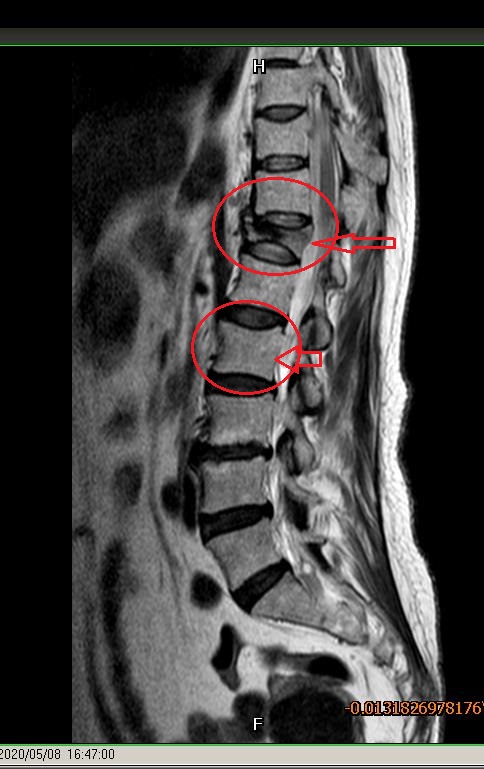

上面红圈中是压缩性骨折椎体,下面是正常椎体

报告是胸12椎体压缩性骨折